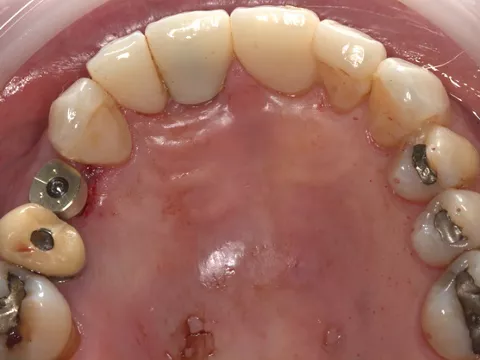

2a. 2b. Preoperative frontal and occlusal view of the lower arch showing multiple missing teeth.

2a

2b